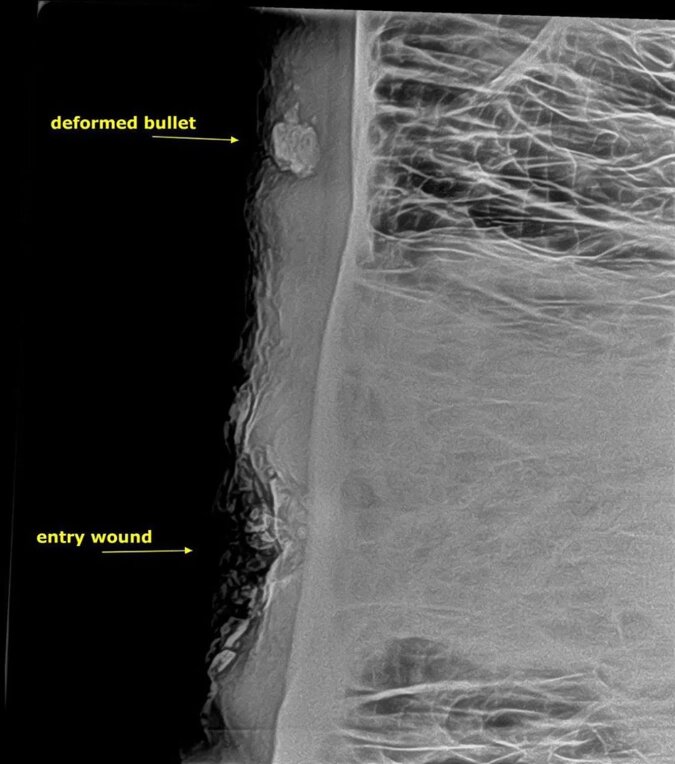

Na miejsce zdarzenia wezwano ekipę weterynaryjną, a słonia unieruchomiono, podając mu środek nasenny. Specjaliści skorzystali z przenośnego aparatu rentgenowskiego.

Rana była powierzchowna, ale bardzo ropiała i słoniowi groziła sepsa. W tej sytuacji czas jest najgorszym wrogiem, dlatego podjęto decyzję, aby nie zabierać zwierzęcia do kliniki, lecz od razu operować.

Jedną z najtrudniejszych rzeczy było usunięcie pocisku, który utkwił w środku. Po jego usunięciu ranę zdezynfekowano i zszyto. Weterynarze poczekali, aż słoń się obudzi, aby upewnić się, że zwierzęciu nic nie jest.